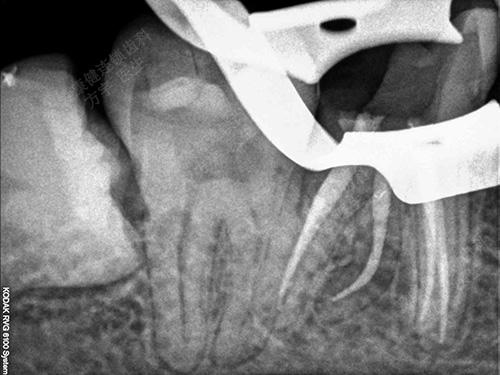

术中